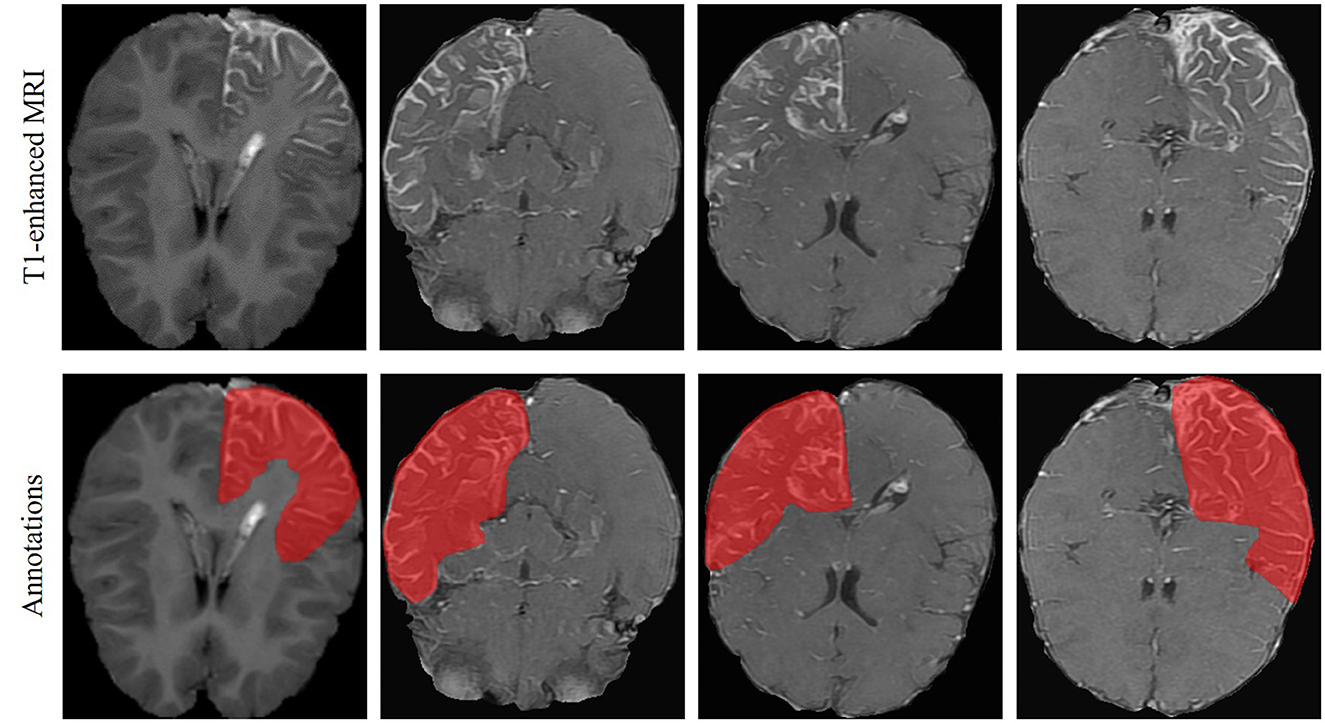

Objectives: Sturge-Weber syndrome (SWS) is a congenital neurological disorder occurring in the early childhood. Timely diagnosis of SWS is essential for proper medical intervention that prevents the development of various neurological issues. Leptomeningeal angiomas (LA) are the clinical manifestation of SWS. Detection of LA is currently performed by manual inspection of the magnetic resonance images (MRI) by experienced neurologist, which is time-consuming and lack of inter-rater consistency. The aim of the present study is to investigate automated LA detection in MRI of SWS patients. Methods: A Mamba-based encoder-decoder architecture was employed in the present study. Particularly, a multi-scale multi-scan strategy was proposed to convert 3-D volume into 1-D sequence, enabling capturing long-range dependency with reduced computation complexity. Our dataset consists of 40 SWS patients with T1-enhanced MRI. The proposed model was first pre-trained on a public brain tumor segmentation (BraTS) dataset and then fine-tuned and tested on the SWS dataset using 5-fold cross validation. Results and Conclusion: Our results show excellent performance of the proposed method, e.g., Dice score of 91.53% and 78.67% for BraTS and SWS, respectively, outperforming several state-of-the-art methods as well as two neurologists. Mamba-based deep learning method can automatically identify LA in MRI images, enabling automated SWS diagnosis in clinical settings.